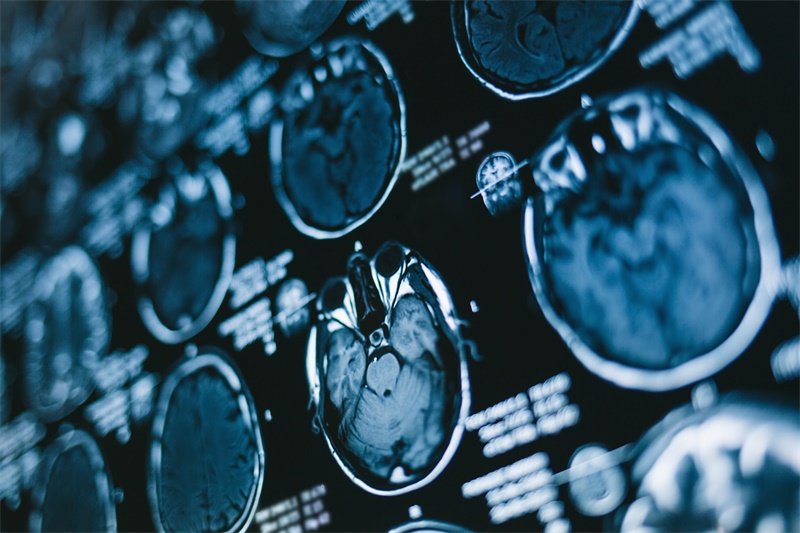

鞍区占位性病变是指发生在大脑鞍区的各种病变,这里是脑部重要的神经结构与内分泌系统交汇的地方。随着现代医学技术的发展,越来越多的患者对鞍区占位性病变有了更深入的了解。这些病变可能表现出不同的临床症状,依据其性质与发展阶段,治疗方案也大相径庭。

鞍区是指脑下垂体所在的位置,即位于蝶骨鞍部的区域。这一区域不仅包括脑下垂体,还涉及到重要的神经通路和血管结构。当发生占位性病变时,通常会表现为各种症状,严重影响患者的生活质量。

鞍区占位性病变可以是多种类型的,包括脑下垂体瘤、鞍区囊肿、动脉瘤等等。这些病变可能会压迫周围正常组织,导致各种神经系统症状,例如视力障碍、头痛、内分泌失调等。